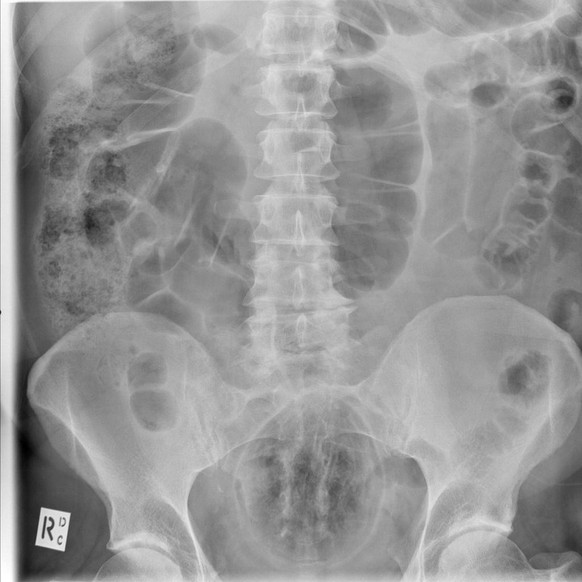

Einer Aubergine

Das Lebensmittel ist auf der Aufnahme für Laien nicht so gut zu erkennen, aber dennoch gut genug: Hier wurde eine Aubergine rektal eingeführt.

Blöderweise bedeutet die zulaufende Form der Aubergine, dass sie sich, einmal eingeführt, immer weiter in den Körper hineinschieben kann. So bleibt für den Auberginen-Freund also nur ein Besuch in der Notaufnahme.